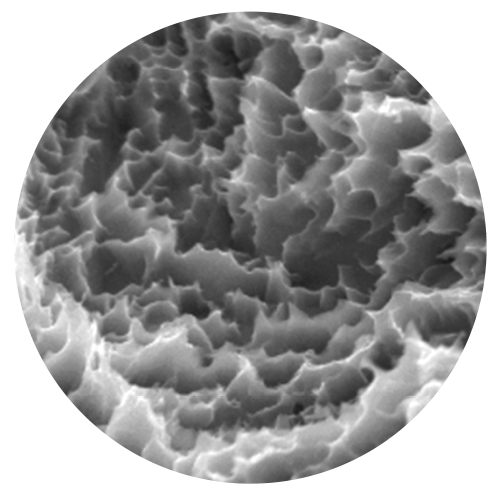

Tratamiento de superficie con Titansure